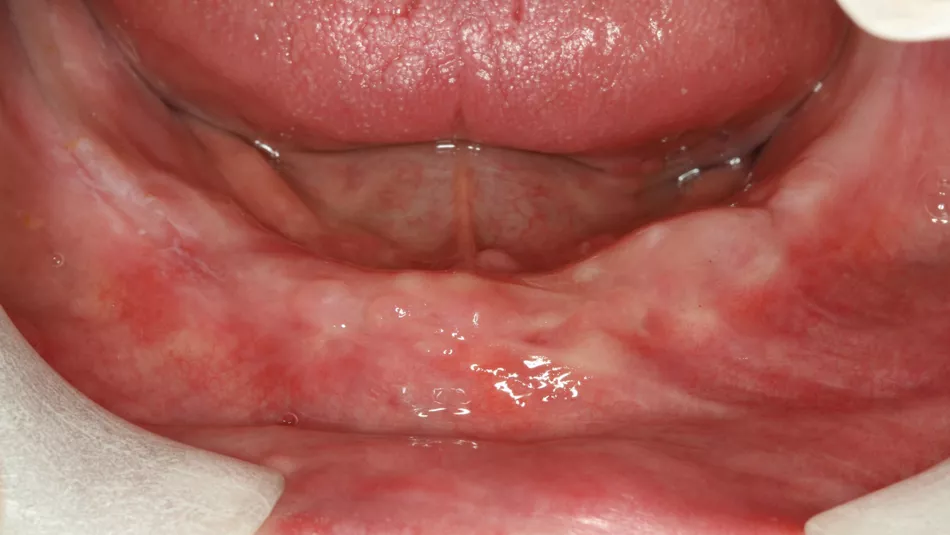

Initial situation: A 79-year-old male patient, wanted to be treated with the minimal amount of surgical procedures, and his main wish was to be able to chew again properly. He was very cost sensitive and aesthetics was for him irrelevant.

Treatment: The treatment plan was performed with a computer software and included the use of four straight Straumann® BLT implants in the lower jaw. Following local anesthesia, and a mid-crestal incision was done. The flap was raised with minimal trauma, the inflamed tissue was removed, and the bone level was adjusted. The implant bed was prepared with the help of a guide and the manufacturer’s protocol was followed. Two implants were placed behind the mental foramina and two in front of it, providing an ideal spread. The placement of implants in resorbed bone led to the need of bone augmentation around the exposed surfaces of the implant. After the surgical procedures, the bite registration was performed, and the impression was sent to the laboratory. Couple of hours later, the temporary prosthesis was placed on the patient and the occlusion was checked.